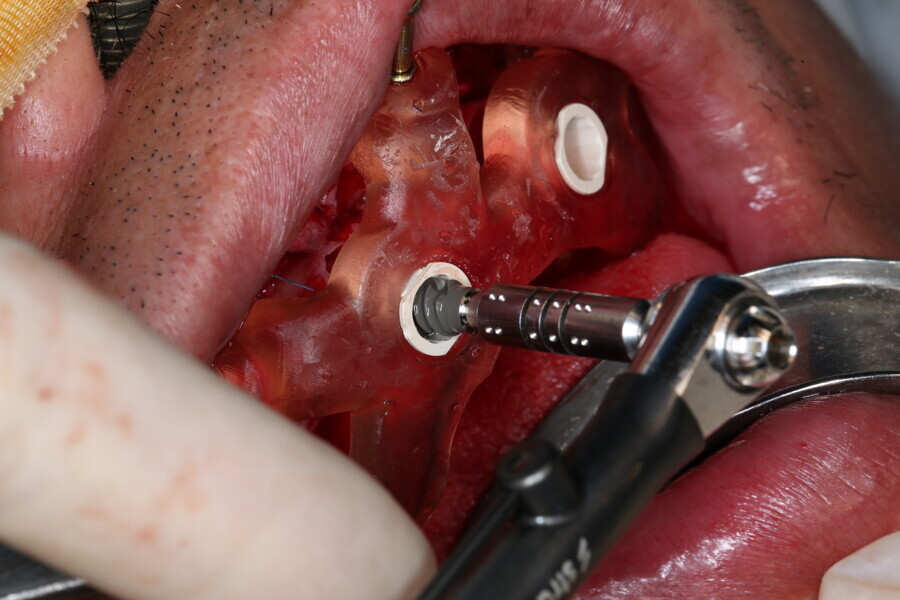

Compromised maxillary dentition treated with Straumann Pro Arch and a digital workflow